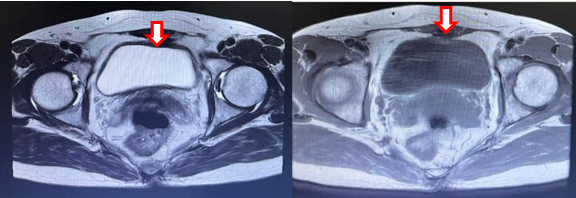

- Cộng hưởng từ tiểu khung:

Hình 3: Chụp cộng hưởng từ ổ bụng, tập trung tiểu khung (13/06/22): Hình ảnh u bàng quang T2aNxMx, vị trí 7h có nốt kích thước 12x16mm (mũi tên đỏ), trong lòng có hình ảnh sonde tiểu (mũi tên xanh), không có sỏi

- Cộng hưởng từ ổ bụng:

Hình 4: Cộng hưởng từ ổ bụng (02/02/23): Không thấy tổn thương nghi ngờ thứ phát tại bàng quang (mũi tên)

Hình 5: Cộng hưởng từ tiểu khung (02/02/23): Hình ảnh dày nhẹ thành bàng quang quanh chu vi (mũi tên). Hiện không thấy tổn thương nghi ngờ thứ phát